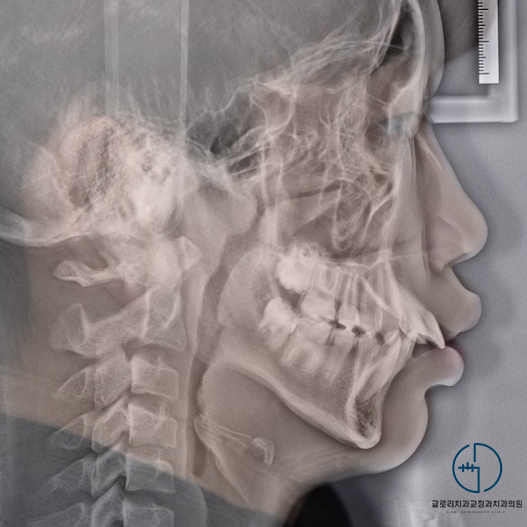

엑스레이 사진을 살펴봐도

꽤 좋아진 것을 볼 수 있는데요.

후방이동을 통해 긴밀하게 배열되어

전체적으로 안정감 있는 입매를 얻게 되었네요^^